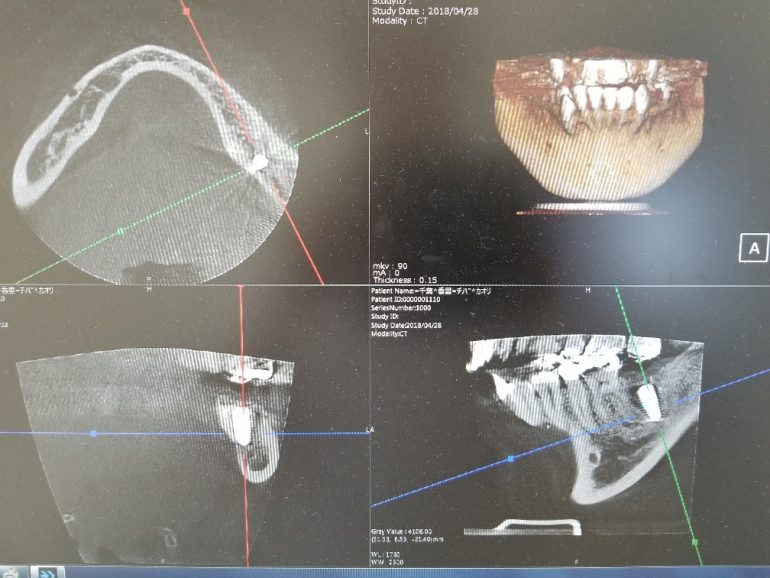

インプラントオペ

本日のオペ オペ前~オペ後 2回のオペに分けてインプラント埋入しました。…